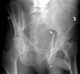

Acetabular fracture

Fractures of the acetabulum occur when the head of the femur is driven into the pelvis. This injury is caused by a blow to either the side or front of the knee and often occurs as a dashboard injury accompanied by a fracture of the femur.The acetabulum is a cavity situated on the outer surface of the hip bone, also called the coxal bone or innominate bone. [Source: Wikipedia ]